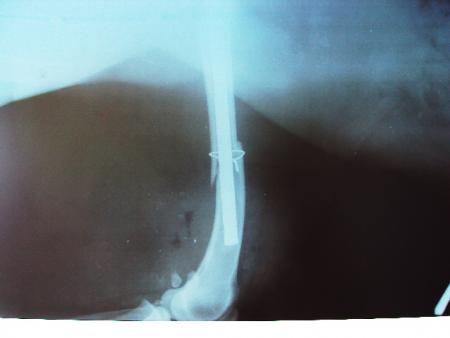

Бела преди приемането в клиниката.

Първите две операции платихме ние, а третата я направиха благотворително от клиниката. Засега се справяме с парите. Ако всичко мине благополучно й предстоят още три операции за изваждане на железата, но... нека да стигнем до там!

Това са снимки на Бела от вторник, вчера нямах сили да я снимам, станала е кожа и кости... Много ми е мъчно!